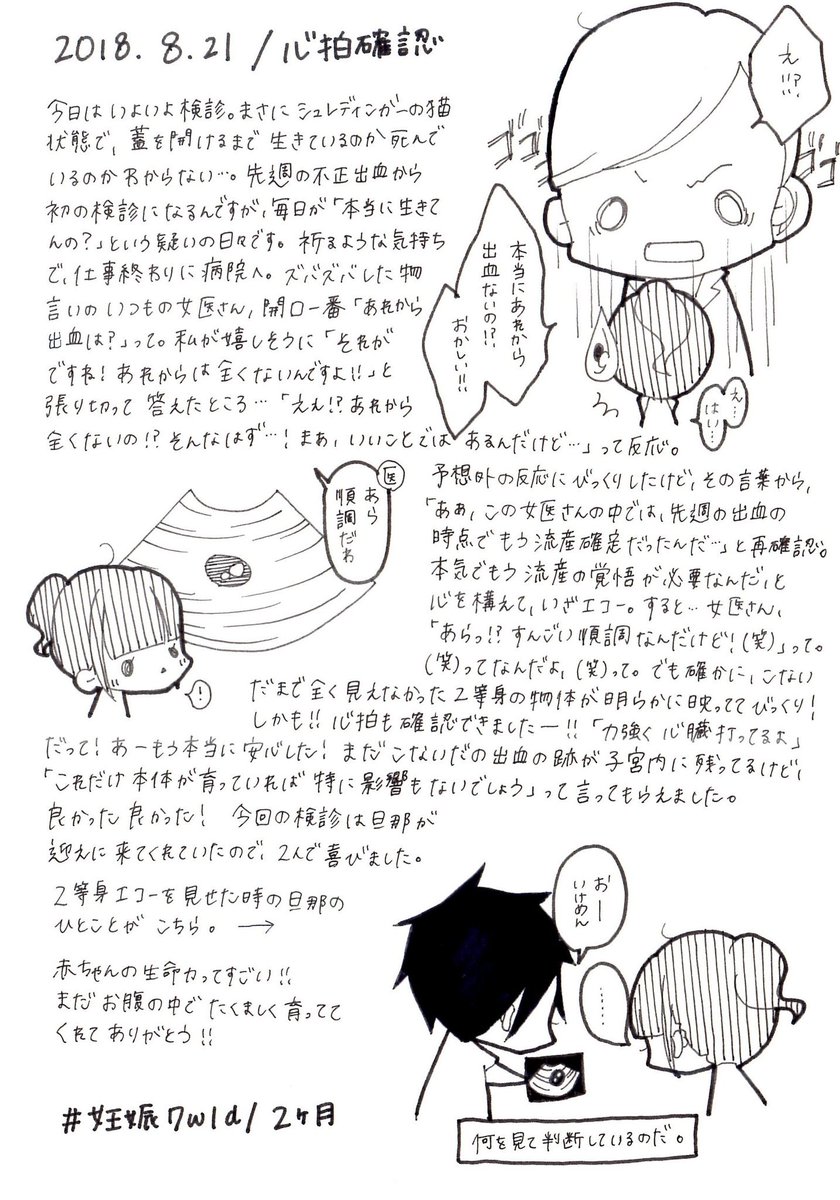

2018.8.21 流産宣告から1週間。 あれから出血も腹痛もなく健診の日が来たためクリニックへ。 そこで見たものは… #育児漫画 #育児日記 #妊娠 #妊娠初期 #心拍確認 #エコー #妊娠2ヶ月 pic.twitter.com/MZRqLfdoJX

2019-08-15 21:16:13 拡大

拡大

拡大

拡大